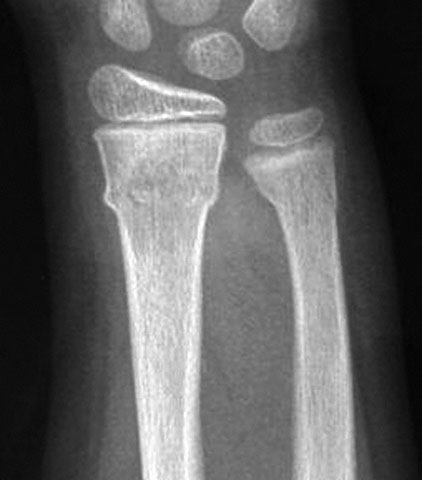

A 15-year-old girl is brought to the emergency department 1 hour after she fell onto her outstretched right arm while playing soccer. She experienced immediate pain. She says she did not think the injury was serious and was able to finish the game. She has not had weakness, numbness, or any other symptoms in her right hand and wrist. On arrival, she is in no distress. Her pulse is 60/min, respirations are 12/min, and blood pressure is 110/60 mm Hg. Examination of the right upper extremity shows moderate tenderness over the distal radius. There is no swelling, erythema, or deformity. Capillary refill time in the fingers of the right hand is 2 seconds. An x-ray of the right wrist is shown. Which of the following is the most appropriate next step in management?